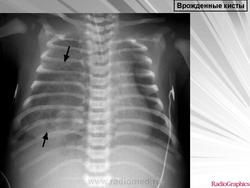

Легочные кисты.

Приложения:

1.ki_.slayd107.jpg2.ki_.slayd108.jpg3.ki_.slayd109.jpg